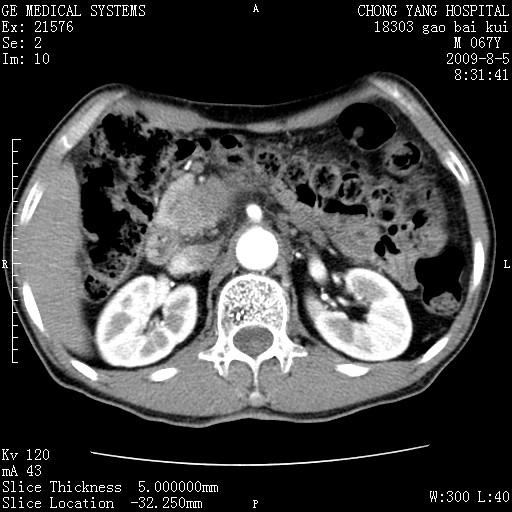

这个也过了,考虑胰腺钩突癌或壶腹癌,不除外胰管粘液乳头瘤伴胰管扩张,肝内胆管积气.

1)考虑胰头癌或壶腹癌并胰管扩张。2)肝外胆管扩张、积气,胆囊影未见;考虑术后改变。3)胃壁增厚?建议必要时行胃镜检查。

考虑胰头癌并十二指肠受侵。